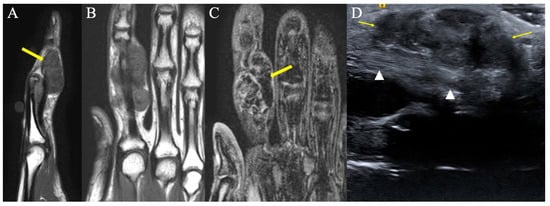

2.2.2. Imaging Appearance

2.8.2. Imaging Appearance